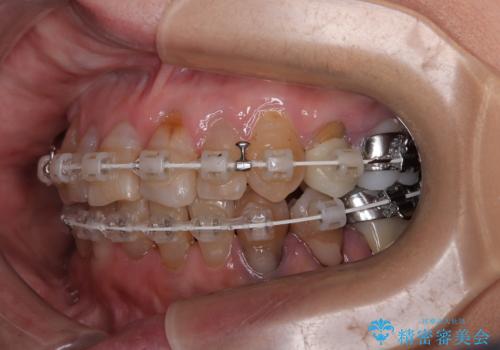

- 長年気にしていた捻れた前歯が欠けたとのことで来院された患者様です。

矯正治療に抵抗があったそうですが、前歯が欠けたことをきっかけに、矯正治療で歯列を整えた上で、セラミッククラウン治療を行う決心が付いたとのことでした。

デコボコが強いため、ブリッジや残根となっている部分のスペースを利用して歯列を整え、変色や欠けている歯をオールセラミッククラウンによる補綴治療を行うこととしました。